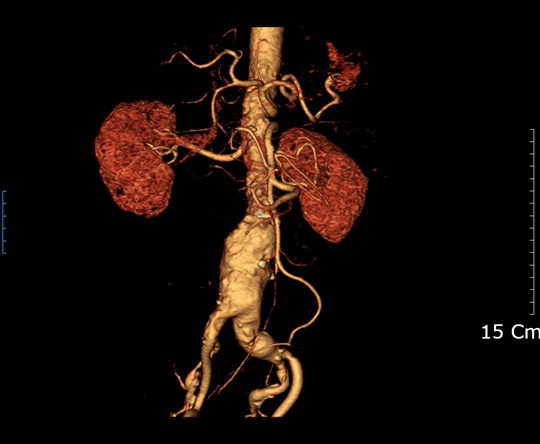

동맥류란 정상 동맥보다 직경이 50% 이상 증가하는 상태를 말한다. 쉽게 말해 동맥이 풍선처럼 부풀어 오르는 것이다. 인체에서 가장 큰 동맥인 복부 대동맥의 정상 직경은 약 2㎝인데 이 복부 대동맥이 50% 이상 굵어져 3㎝ 이상이 되면 복부 대동맥류로 본다.

복부 동맥류는 대부분 건강 검진 등 다른 검사 중에 우연히 발견된다. 복부 동맥류를 검사하는 방법으로는 비침습적인 초음파 검사가 우선이며, 여기에서 복부 동맥류가 관찰되면 컴퓨터 단층촬영(CT)이나 자기공명영상(MRI) 검사를 시행한다.

치료는 개복해 복부 동맥류 발생 부위를 인조 혈관으로 대체하는 고전적 방법과 방사선으로 투시하면서 스텐트·도관을 삽입하는 방법으로 나뉜다. 개복 복원술은 개복에 따른 복강 및 폐·심혈관계 합병증이 스텐트·도관 삽입술보다 높지만, 안정적인 수술이 이뤄지면 이후 5년 내에 CT 검사를 통한 주위 대동맥의 변화를 관찰만 하면 된다.